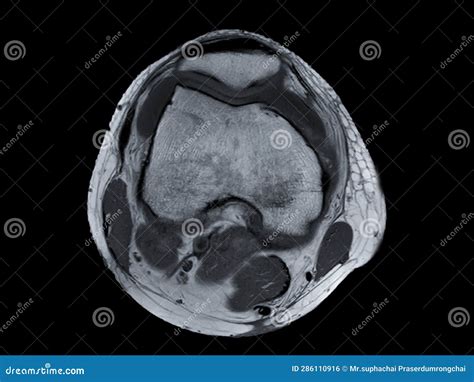

Interpreting the results of a Normal Knee MRI requires a trained radiologist. The images will be reviewed to identify any abnormalities. Here are some key structures that are typically examined:

Bones

The MRI will show the bones of the knee, including the femur, tibia, and patella. Any fractures, tumors, or other bone abnormalities will be visible.

Menisci

The menisci are C-shaped pieces of cartilage that act as shock absorbers between the femur and tibia. The MRI can show tears or degeneration in the menisci, which are common in athletes and older adults.

• normal knee mri axial